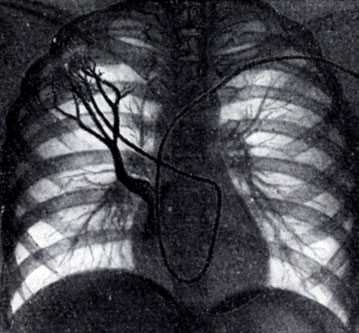

Рис. 1. Общая ангиопульмонография. Контрастное вещество введено катетером. Видны контрастированные сосуды легких. Справа в области ключицы и вдоль позвоночника виден введенный в сердце катетер

Для осуществления общей ангиопульмонографии контрастное вещество в количестве 50—70 мл вводят внутривенно (обычно через локтевую вену) или в полость правого сердца (см. Ангиокардиография) при помощи введенного через вену катетера (рис. 1). При селективной ангиопульмонографии (рис. 2) контрастное вещество вводят в одну из ветвей легочного ствола; для этой цели катетер проводят через правое сердце в легочный ствол и далее в легочную артерию. Для контрастирования одного легкого применяют 20—30 мл контрастного вещества, для исследования одной зоны — 10—15 мл.